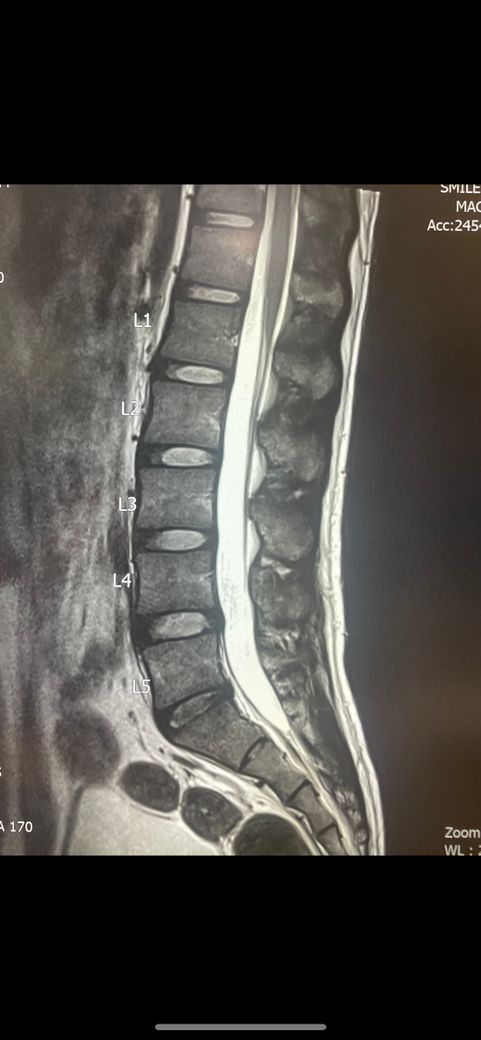

허리디스크 초기 판정을 받았습니다. 도움이되는 운동과 관리방법을 알려주세요. 지금어떤상태인지 초기는 완치 가능한지도 궁금합니다

• 1번 째 사진

허리 추간판의 약간의 돌출이 보이는 상태같습니다.

요추 5번 천추 1번 사이에 디스크내장증이 있어보입니다.

흔히 이야기하시는 디스크는 디스크탈출을 의미하는데 수핵이 탈출한 정도의 디스크는 아니고 디스크 섬유륜 일부층이 찢어지는 디스크내장증이 있는 상태로 보입니다.

디스크 내장증을 그냥 이해하기 쉬우시라고 디스크 초기라고 표현하시는 경우도 있겠습니다.